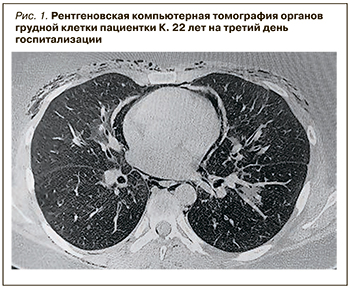

На третий день госпитализации подкожная эмфизема распространилась у пациентки на плечи и предплечья с обеих сторон (больше справа), степень выраженности болей в грудной клетке и одышки не изменилась. Сохранялась фебрильная температура. На повторной рентгенограмме ОГК выявлена подкожная эмфизема, но достоверных данных в пользу пневмоторакса не было. С целью детализации причин эмфиземы и уточнения локализации жидкостного образования была проведена рентгеновская компьютерная томография (РКТ) ОГК, выявившая пневмомедиастинум и пневмоперикард, утолщение париетальных листков перикарда. Были описаны инфильтративные изменения легких по типу «матового стекла», подкожная эмфизема грудной клетки, мягких тканей спины и плеч. Отмечен свободный газ в спинномозговом канале, плевральной полости, скопление гиподенсивного содержимого по верхней поверхности легочного ствола и задней поверхности восходящего отдела аорты (выпот), гиподенсивное образование переднего полюса селезенки (киста?) (рис. 1).

На третий день госпитализации подкожная эмфизема распространилась у пациентки на плечи и предплечья с обеих сторон (больше справа), степень выраженности болей в грудной клетке и одышки не изменилась. Сохранялась фебрильная температура. На повторной рентгенограмме ОГК выявлена подкожная эмфизема, но достоверных данных в пользу пневмоторакса не было. С целью детализации причин эмфиземы и уточнения локализации жидкостного образования была проведена рентгеновская компьютерная томография (РКТ) ОГК, выявившая пневмомедиастинум и пневмоперикард, утолщение париетальных листков перикарда. Были описаны инфильтративные изменения легких по типу «матового стекла», подкожная эмфизема грудной клетки, мягких тканей спины и плеч. Отмечен свободный газ в спинномозговом канале, плевральной полости, скопление гиподенсивного содержимого по верхней поверхности легочного ствола и задней поверхности восходящего отдела аорты (выпот), гиподенсивное образование переднего полюса селезенки (киста?) (рис. 1).